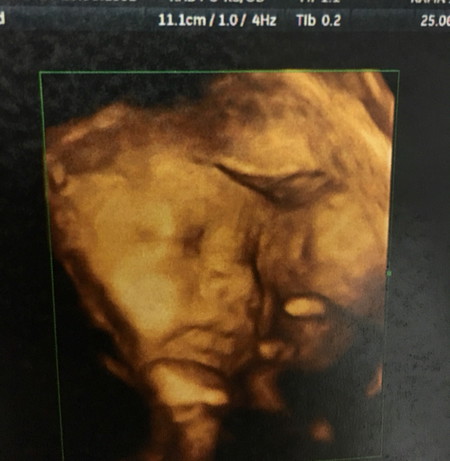

ครรภ์ 30 สัปดาห์น้ำหนักทารก 1,955 กรัม คุณหมอบอกเกินเกณฑ์มาหน่อยๆๆ??? ปล.น้ำหนักแม่ขึ้นมาแต่ 9 โลเอง???